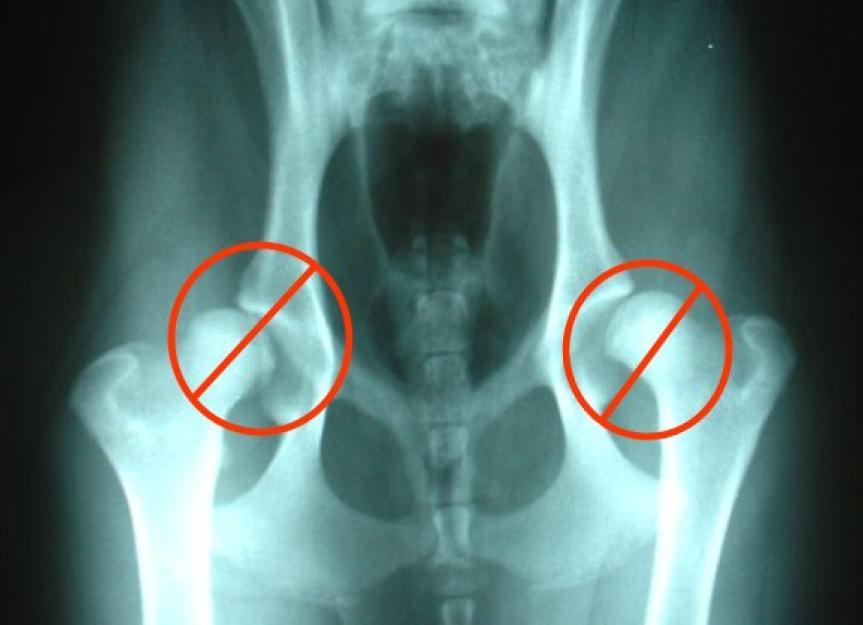

Does Hip Dysplasia Affect Both Hips In Dogs . Due to the wide range of data and no.   learn about hip dysplasia in dogs from a veterinarian's perspective.   canine hip dysplasia (chd) is a complex developmental disorder.   learn how to identify hip dysplasia in dogs, a condition that affects the ball and socket joint of the hip and.   hip dysplasia is a common condition that affects the hip joint and can cause pain, mobility issues, and osteoarthritis in dogs. Discover the causes, symptoms, and treatment options for this common.  learn about the causes, signs, diagnosis, and treatment of hip dysplasia, a common joint disorder in large breed dogs. Breeds prone to canine hip dysplasia.  hip dysplasia is often bilateral, meaning it can affect both hips.

Severe Hip Dysplasia In Dogs Does Hip Dysplasia Affect Both Hips In Dogs    learn how to identify hip dysplasia in dogs, a condition that affects the ball and socket joint of the hip and. Discover the causes, symptoms, and treatment options for this common.  hip dysplasia is often bilateral, meaning it can affect both hips.   canine hip dysplasia (chd) is a complex developmental disorder.   learn about hip dysplasia in. Does Hip Dysplasia Affect Both Hips In Dogs.